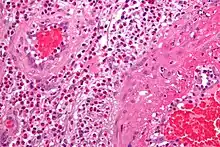

• Some types of vasculitis display leukocytoclasis, which is vascular damage caused by nuclear debris from infiltrating neutrophils.[12] It typically presents as palpable purpura.[12] Conditions with leucocytoclasis mainly include hypersensitivity vasculitis (also called leukocytoclastic vasculitis) and cutaneous small-vessel vasculitis (also called cutaneous leukocytoclastic angiitis).